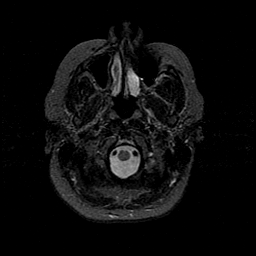

MR Study #1 -- Slice #7